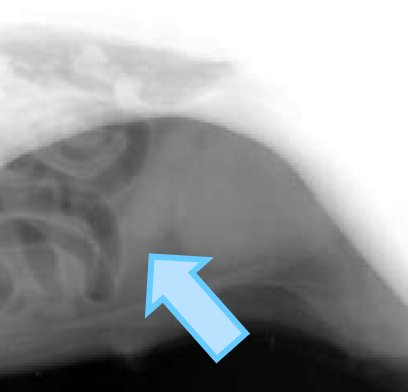

liver

splenic tail

splenic head

fundus and body

pylorus